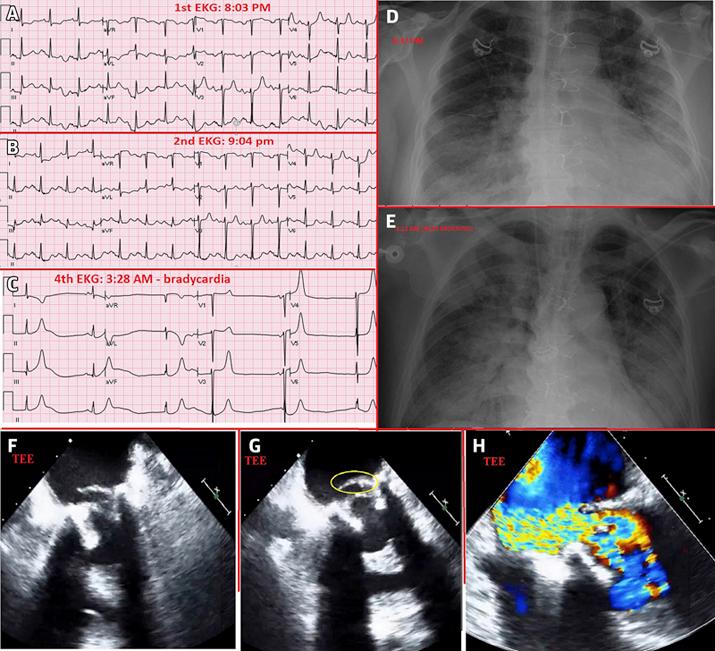

Tragic End or Expected Destiny?: Pulmonary Edema Due to Sewing Ring Dehiscence of Bioprosthetic Mitral Valve.

The present case is unique because it describes transcatheter mitral valve replacement with a valve-in-valve procedure in an emergent setting of pulmonary edema and cardiogenic shock. Although transcatheter mitral valve replacement is in its initial phase, it remains a viable option in an emergency. Further research is needed to evaluate the short term and long-term outcomes. ().